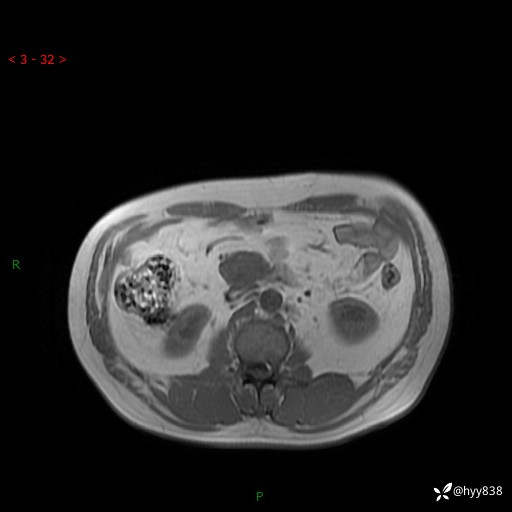

腹部CT平扫

MRI(T1WI+T2WIfs+DWI)